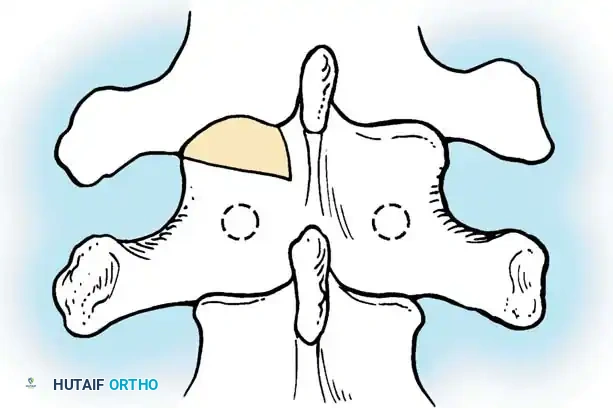

The Moe Technique (Thoracic Spine)

The Moe technique is a highly effective method for achieving intra-articular arthrodesis in the coronally oriented thoracic facet joints.

Fig. 38-26: The Moe technique of thoracic facet fusion, demonstrating the creation of hinged bone flaps.

- Expose the spine fully to the tips of the transverse processes.

- Using a sharp osteotome or Cobb gouge, begin a cut over the cephalad articular process at the base of the lamina.

- Carry this cut along the transverse process almost to its tip. Bend this cortical fragment laterally so it lies between the transverse processes, ideally leaving it hinged on its lateral periosteal attachment to preserve local vascularity.

- Thoroughly denude all articular cartilage from the superior articular process using a sharp curet.

- Make a secondary cut in the superior articular facet, working medially to laterally, producing another hinged fragment.

- Pack the resulting intra-articular defect tightly with cancellous bone graft.